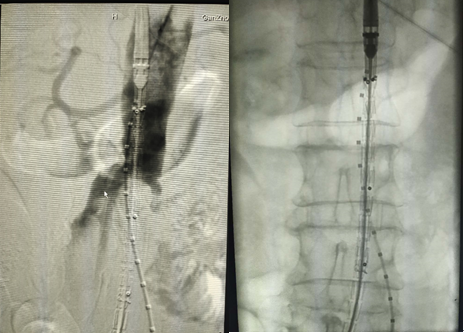

7.主體支架釋放后造影,左右髂動(dòng)脈分支通暢

8、調(diào)整好左右兩邊導(dǎo)管導(dǎo)絲,引入左右髂動(dòng)脈分體支架

9、主體支架和左右分體支架釋放后,發(fā)現(xiàn)支架貼合不佳,球囊后擴(kuò)

10、在3D打印血管的輔助下完成腹主動(dòng)脈瘤的覆膜支架腔內(nèi)隔絕術(shù),最后造影結(jié)果